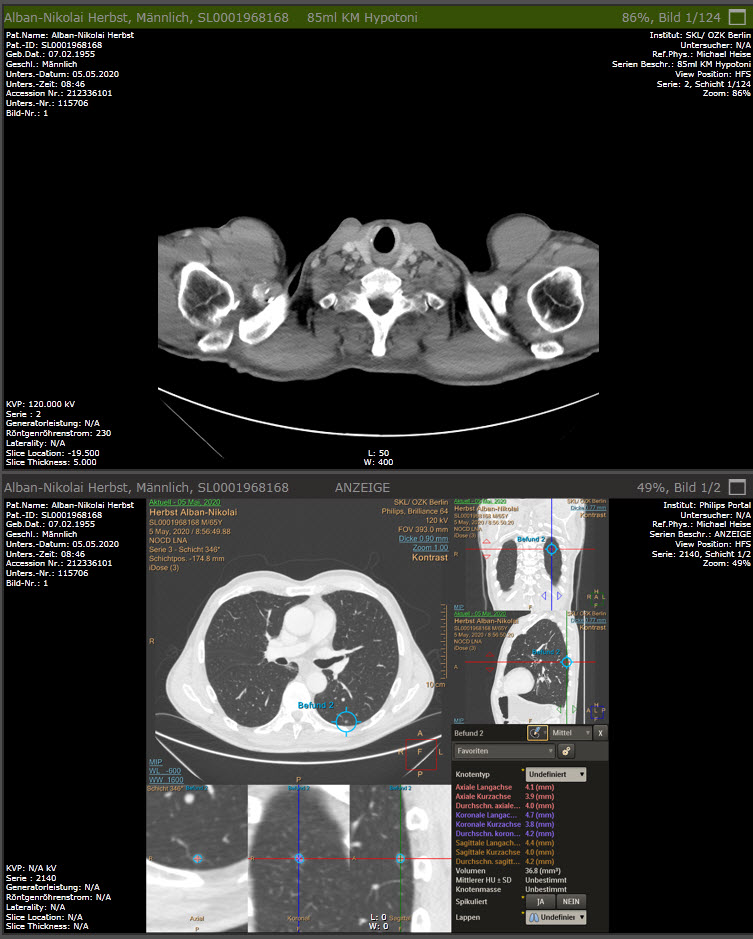

Hier kann man gut sehen, wie so ein unter der Haut liegender Port genau ausschaut und eingebaut ist.

Wenn ich das richtig sehe, sitzt der BioPort rechts – und nicht links oder? Wie ursprünglich geplant und ebenso OP -durchgeführt, von ihrem, ach so sympathischen Arzt.. — nebensächlich, darauf hinzuweisen – ich weiß – – die Gewichtsabnahme ist zunächst kein großes Problem, eine mögliche Stoffwechselveränderung – in die, sagen wir mal: „falsche Richtung“ – könnte allerdings schwierige Folgen haben – aber daran möchte jetzt NIEMAND denken.. — na denn: Leinen los und ab geht die Reise ….alles Gute …RIvS …

Neinnein, rechts – hatte ich das nicht geschrieben? Doh, >>>> habe ich (schnell noch mal nachgelesen). Die rechte Seite war also von Anfang an von meinem Chirurgen so geplant. Siehe auch >>>> dort in Frau Nielsens Kommentar.

ja, lesen kann ich – außerdem kenne ich mich ziemlich gut aus, was diese medizinischen Dinge angeht — also: weiter oben (ja, hier in diesem Bericht) – steht, da, wo sie über ihren (Brustkorb) Muskelkater berichten:….Was an dem in die LINKE Unterschultermuskulatur, unter die Haut implantierten BioPort liegen dürfte….etc. – sorry, jetzt bin ich pingelig, ist nicht bös gemeint….es hat mich nur etwas verwirrt, weil das zugehörige Foto zeigt ja die richtige Seite (rechts)….— Gruß, RIvS…